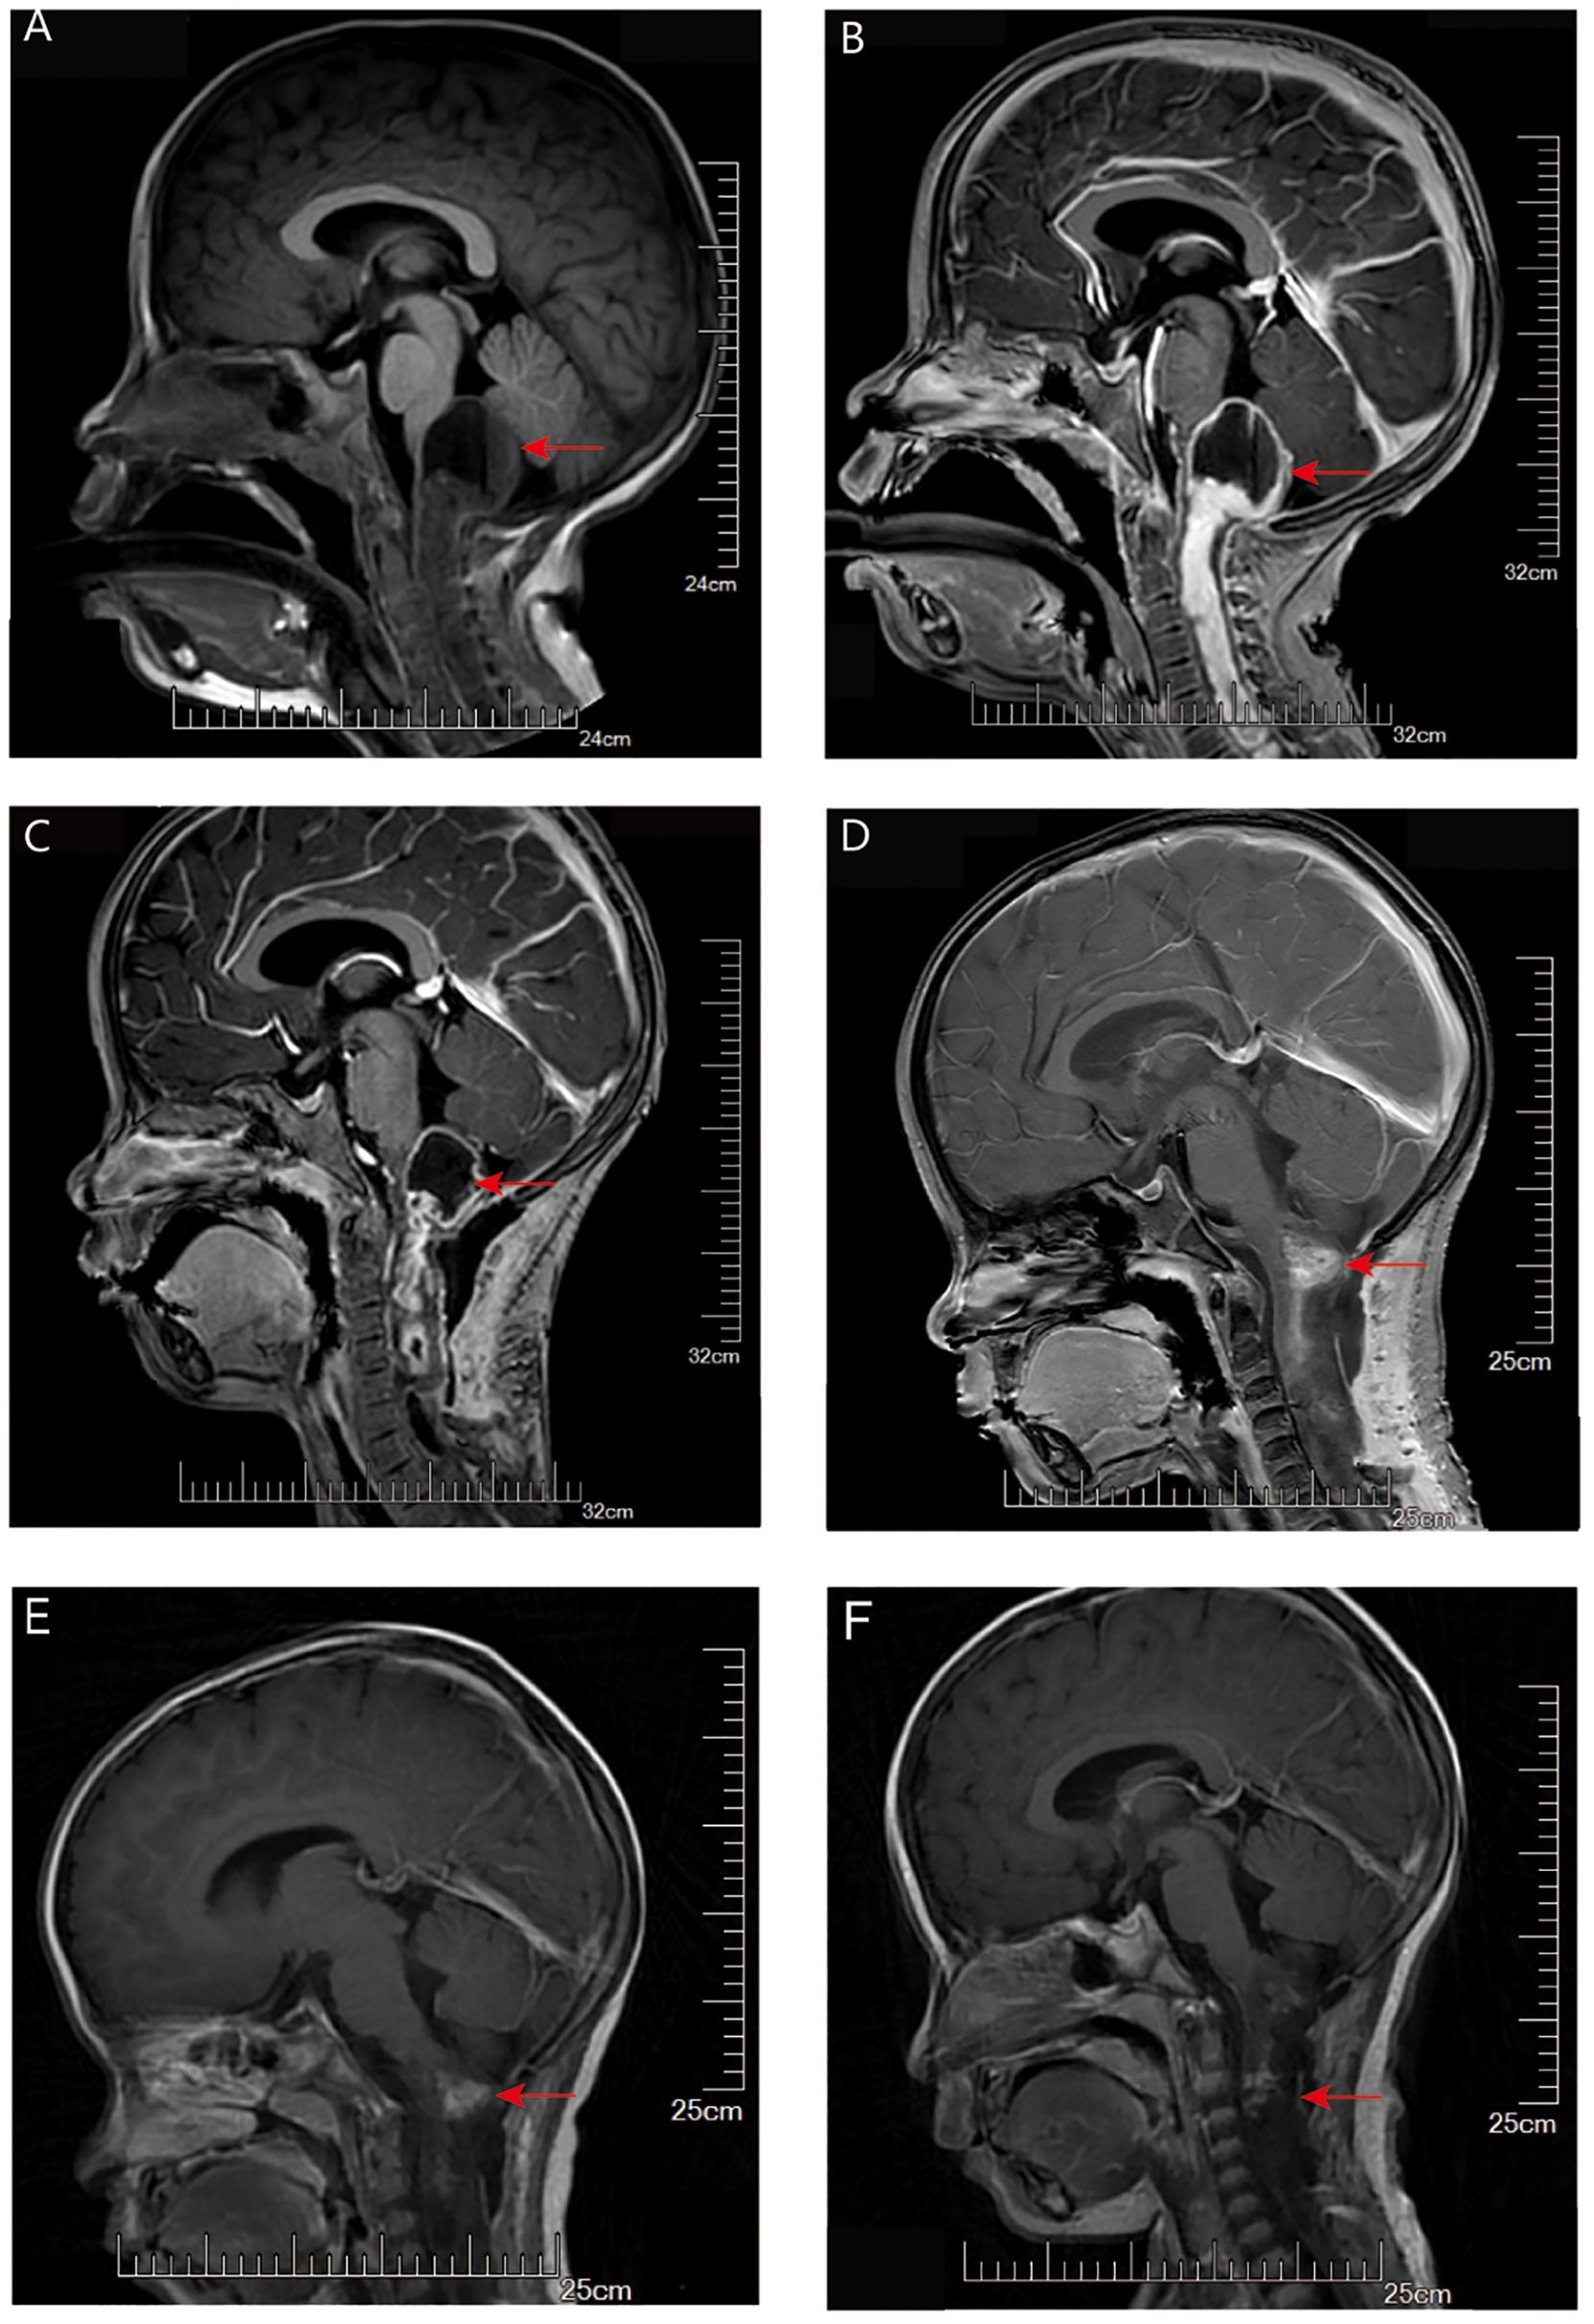

The mitogen-activated protein kinase (MAPK) signaling pathway plays roles in cell proliferation, differentiation, and apoptosis, all crucial for cellular transformation. It's no surprise that MAPK alterations are prevalent in numerous tumors. Several critical genes in the MAPK signaling pathway, including BRAF, FGFR, and NF1, are mutated in brain tumors. For example, FGFR1 mutation or rearrangement has been described in pilocytic astrocytoma, diffuse astrocytoma, and dysembryoplastic neuroepithelial tumor (DNT). These MAPK-activated brain tumors are benign and seldom progress to malignancies, with the mechanisms driving this rare transformation not yet fully understood. In this study, we present two cases of high-grade glioma characterized by a single activating mutation of FGFR1 and massive chromosome loss (near-haploid genome). Similar haploidy is found in 3 additional high-grade astrocytoma by literature review, all harbor a single gene mutation in the MAPK pathway. We propose that the massive chromosome loss might serve as a significant mechanism contributing to the unusual malignant transformation of benign brain tumors activated by the MAPK pathway.